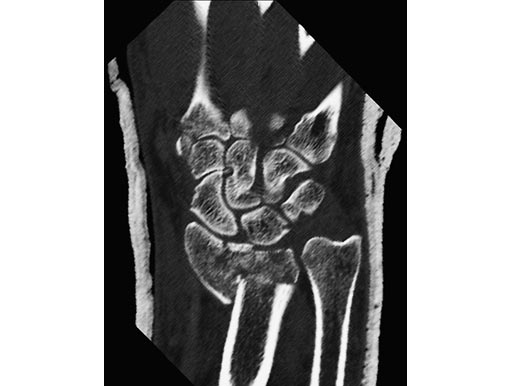

54-year-old female with 23-C3 fracture after fall

External fixator due to severe soft-tissue trauma. Palmar plate 1 week later. .